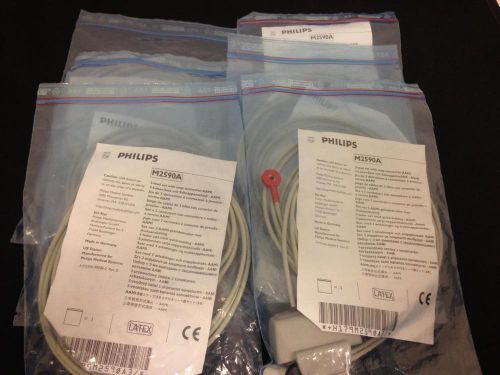

**Lot of 6** Philips M2590A 3-Snap Leadset for Phililps M2601A ***OEM NEW***